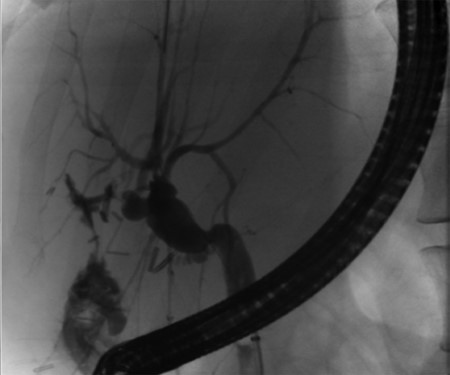

Follow-up ERCP 4 weeks later displaying resolution of all abnormalities.

A 35-year-old female with a medical history significant for acute biliary pancreatitis status post laparoscopic cholecystectomy, presented to the surgery clinic as a new consult for a large cystic liver mass with increasing abdominal pain for 2 weeks. Patient reported suffering from severe pain in right chest, shoulder and diffuse abdominally that worsened with standing. Patient complained of inability to inspire due to pain and a 10-pound weight gain over 2 months. She confirmed decreased appetite especially with solids, nausea and emesis, alternating constipation and diarrhea, bruising, and pruritus at night. Computed tomography (CT) scan demonstrated a peripherally septated 10 x 7 cm cystic mass in the liver with intrahepatic biliary dilation (Fig. 1). The patient was referred for endoscopic retrograde cholangiopancreatography (ERCP) to establish preoperative biliary anatomy and was found to have moderate compression of the common hepatic duct managed with a right hepatic biliary endoprosthesis (Fig. 2); no obvious communication of the biliary tree with the cystic lesion was seen. Patient symptoms persisted despite optimizing with a protein-rich liquid diet; thus, the decision was made to proceed with the surgical plan for an open partial central hepatectomy. The patient was taken to the operative theater. After induction of general anesthetic, an upper midline incision was made. Inspection of the abdomen and liver showed no metastatic lesions grossly or with ultrasonographic imaging. The cyst was visible upon entry into the abdomen with no solid component to the mass in proximity to the cystic neoplasm. The second portion of the duodenum was adherent to the cyst with inflammatory adhesions and was quite boggy. A partial central hepatectomy was performed; a 3 mm biliary duct was found communicating to the cyst only with no drainage to the minimal liver parenchyma that was removed (Fig. 3). The cyst was resected en-bloc and was sent for permanent section (Fig. 4), which diagnosed the tumor as a low-grade mucinous cystic neoplasm measuring 8.5 × 7.2 × 6.4 cm. Microscopy revealed a smooth-walled, multiloculated cyst filled with a yellow-golden, semi-transparent and mucinous fluid (Fig. 5a–c). The cyst was lined by a mucinous epithelium with ovarian-type stroma. No high-grade dysplasia or malignancy was identified. The postoperative course was uneventful, and the patient was discharged on postoperative day 6. At the 4-week postoperative visit, the patient was healing well with some incisional soreness; patient was seen for removal of her biliary endoprosthesis, and ERCP found left sided intrahepatic duct biliary dilatation including a small biliary fistula from the left system (Fig. 6) with the appearance of torque on the extrahepatic biliary tree. A biliary endoprosthesis was left in place, and the patient returned for repeat ERCP 4 weeks later with resolution of all findings (Fig. 7). At present, patient remains alive with no signs of recurrence.